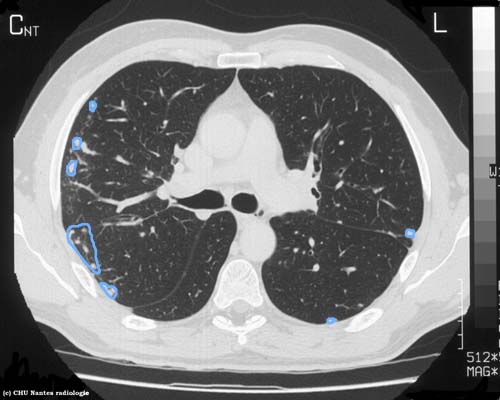

Syndrome interstitiel nodulaire

coupe TDM millimétrique en fenêtre parenchymateuse

syndrome interstitiel nodulaire avec des nodules de topographie périphérique sous pleurale